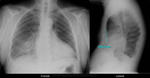

1. На мой взгляд расширения сердечной тени нет, есть её смещение влево.

2. По боковой рентгенограмме, вот кажется мне, что имеем мы дело с воронкообразной грудной клеткой, что видно при осмотре "ад окулус".

исследовании сердце смещено влево на 2-3 см.

ческом исследовании сердце смещено влево более чем на 3 см.

Figure 1. 13-year-old female with pectus excavatum. A. Posteroanterior radiograph. B. Lateral chest radiograph.

Валентин Львович, Вы были правы что имеем дело с воронкообразной грудной клеткой!!! Сам я пациента после не видел, но приходила работница с военкомата, поинтересовался - она подтвердила, сказала что уже отправили в армию, комиссия вынесла что сердце, лёгкие не страдают, с её слов якобы степень смещения II.